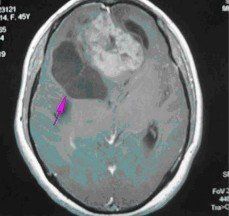

1.星形細胞瘤:為膠質瘤中最常見的一種,約占40%左右。病理分型為Ⅰ級(星形細胞瘤),Ⅱ級(星形母細胞瘤),Ⅲ~Ⅳ級(多形膠母細胞瘤)。Ⅰ~Ⅱ級星形細胞瘤為低度惡性,起病緩慢,腫瘤在CT及MR的表現多為實性或囊性,邊界不清,腫瘤實性部分或囊性結節均可強化。臨床表現與病灶部位不同進行性地出現相應的症狀,並最後出現顱高壓的症狀。Ⅲ~Ⅳ級的多形膠母細胞瘤起病快速,為惡性度最高的腫瘤,多生長於大腦半球,因腫瘤生長迅速,腫瘤中心可有多處壞死及出血,CT及MR均明顯強化。周圍可伴大片腦組織的水腫。

根據其生物學特徵、年齡、性別、好發部位及臨床過程進行分析,在病史及體徵基礎上,採用電生理、超音波、放射性核素、放射學及核磁共振等輔助檢查,定位正確率幾乎是100%,定性診斷正確率可在90%以上。